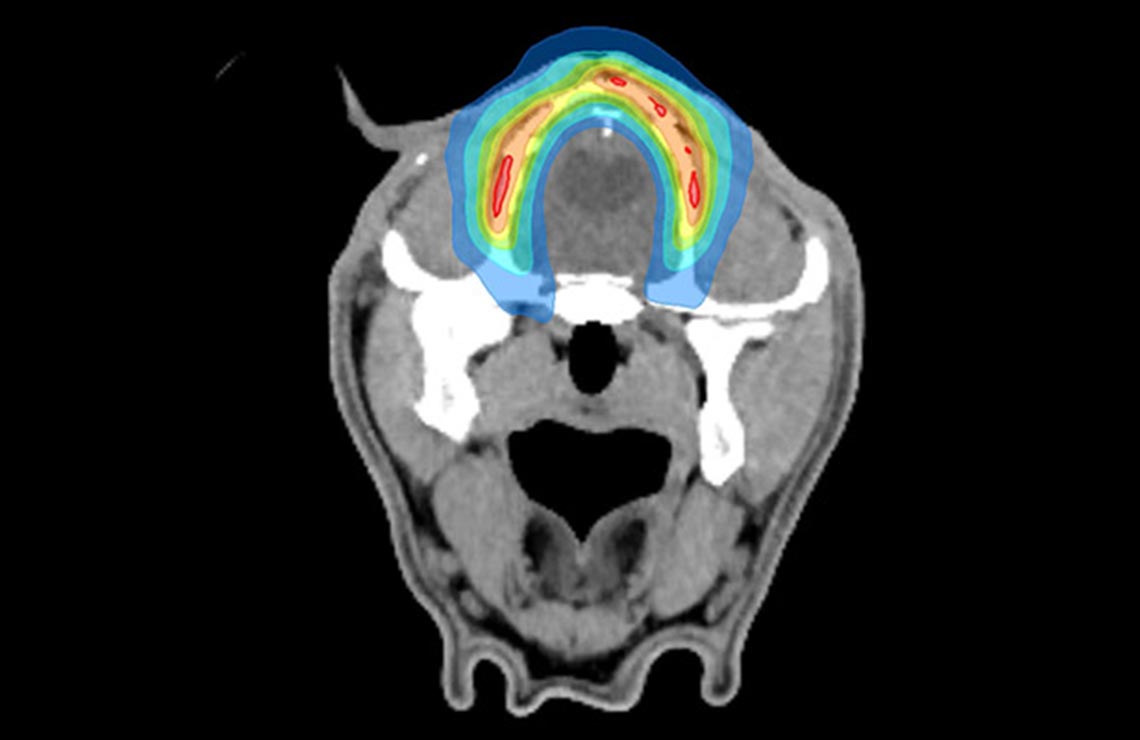

放射線治療はがんの治療でなくてはならないものになっており、手術と異なり痛みや侵襲をほとんど伴わないという特徴を持っています。一方、正常組織に放射線を照射してしまうと副作用が発生してしまうことから、いかに「がん」のみに正確に放射線を照射するかが治療の成否のカギとなります。当院では高精度に放射線を照射することが可能なトモセラピー (Accuray社、TomoHDA) を導入しております。トモセラピーは以下の特徴を持つ放射線治療装置です。

放射線治療機を回転しながら超高速で放射線強度をコントロールすることで、「がん」に対して高精度に放射線を照射することが可能です。